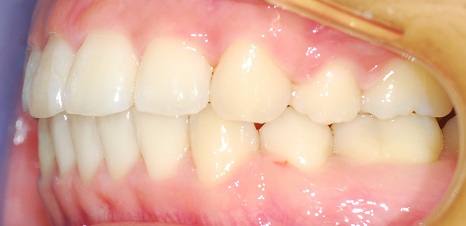

완성된 치아사진 보실게요ㅎㅎㅎ

측면사진